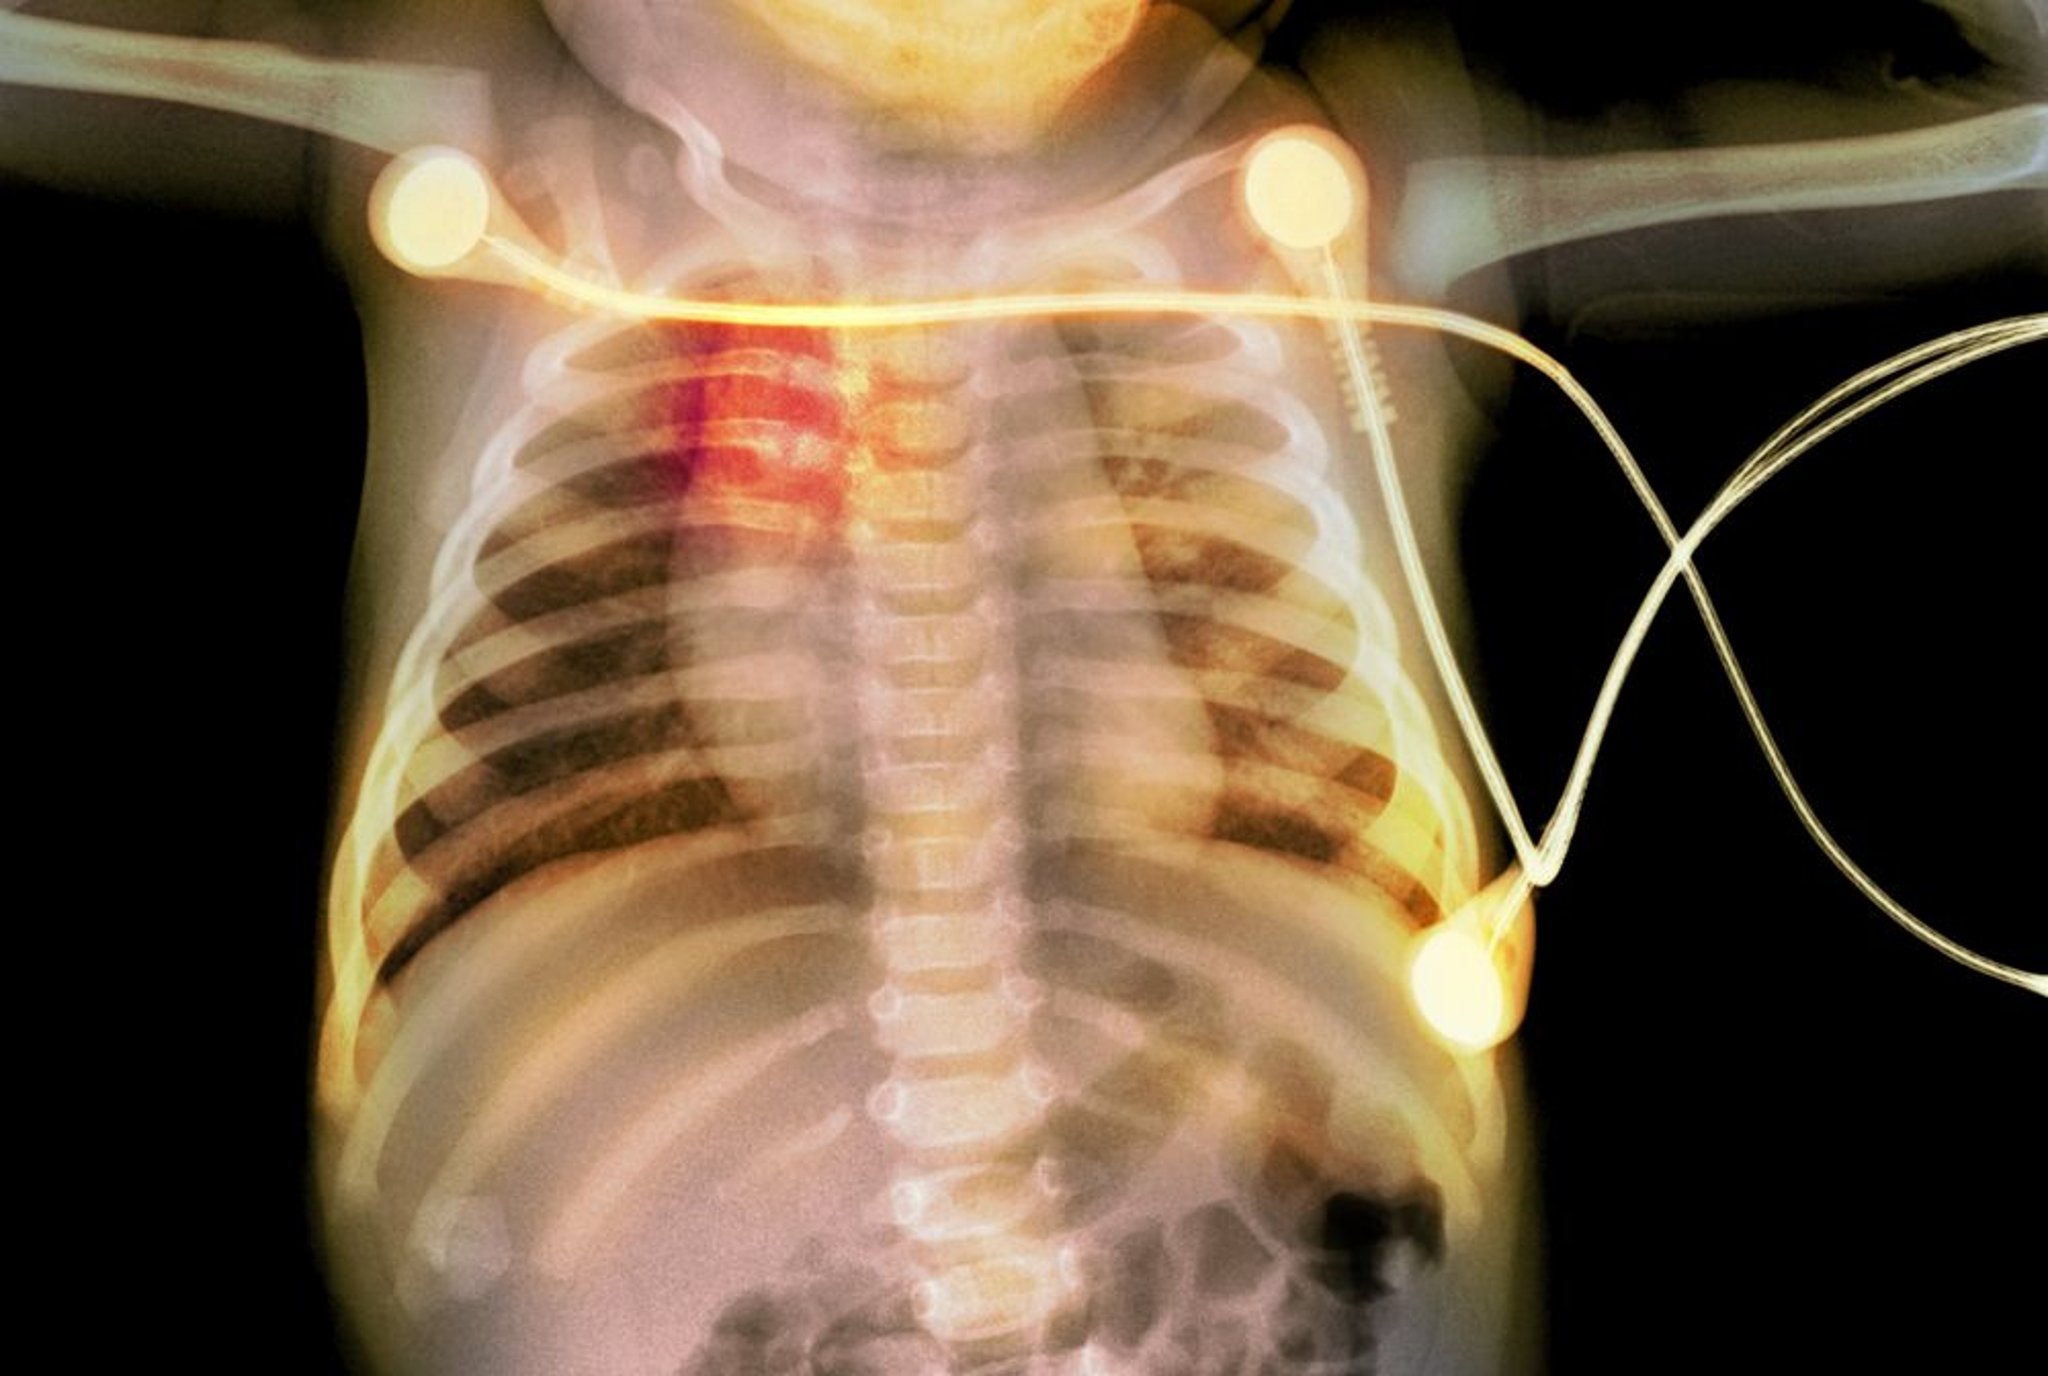

Dieses Röntgenbild zeigt Rippenfrakturen (rot markiert) bei einem Baby, die auf Kindesmissbrauch hinweisen.